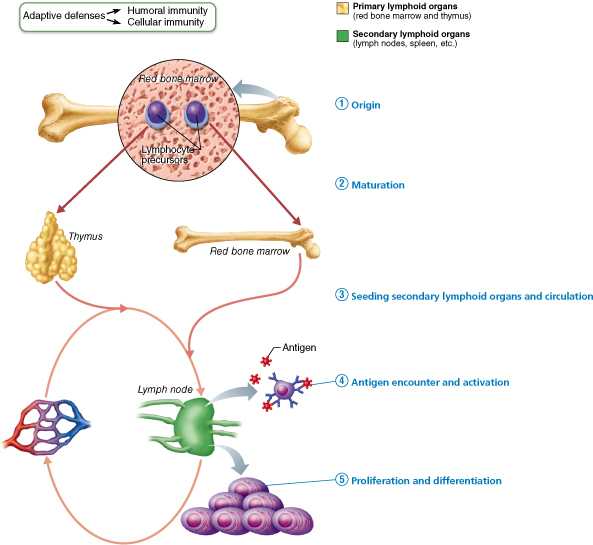

破解谜团:B淋巴细胞发现50年 | 果壳 科技有意思

T淋巴细胞 – 91360智慧病理网